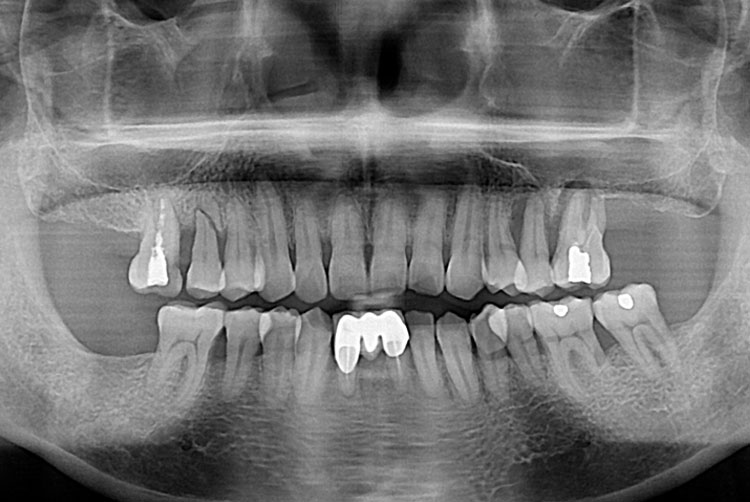

[임플란트] 임플란트

치료전 : 2018-06-14

세종치과는 많은 환자와 다양한 케이스를 바탕으로 항상 편안한 임플란트 수술을 제공하고자 노력하고,

오래동안 튼튼히 쓸 수 있는 임플란트 수술을 가장 큰 목표로 삼고 있습니다.